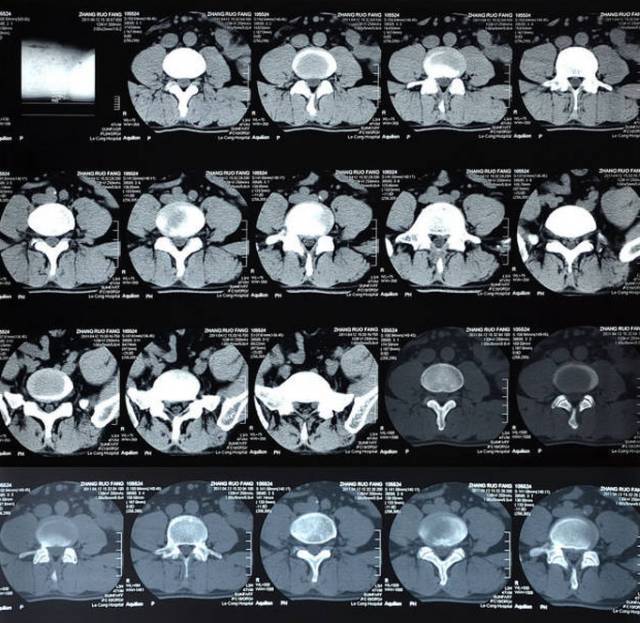

下面小编就介绍下这个正常的腰椎在CT下的解剖结构。平行于椎体终板作腰椎横断CT扫描,正常腰椎

当下,在平时腰部疾患是非常常见的,不过你们可否知道腰椎下面小编就介绍下这个正常的腰椎在CT下的解剖结构。

很有必要要来了解下这个腰椎的正常解剖结构,下面就来介绍下正常的腰椎在CT下的解剖结构。

在生活中腰椎疾病很常见,但是大家是否了解这个腰椎在CT下下面小编就介绍下这个正常的腰椎在CT下的解剖结构